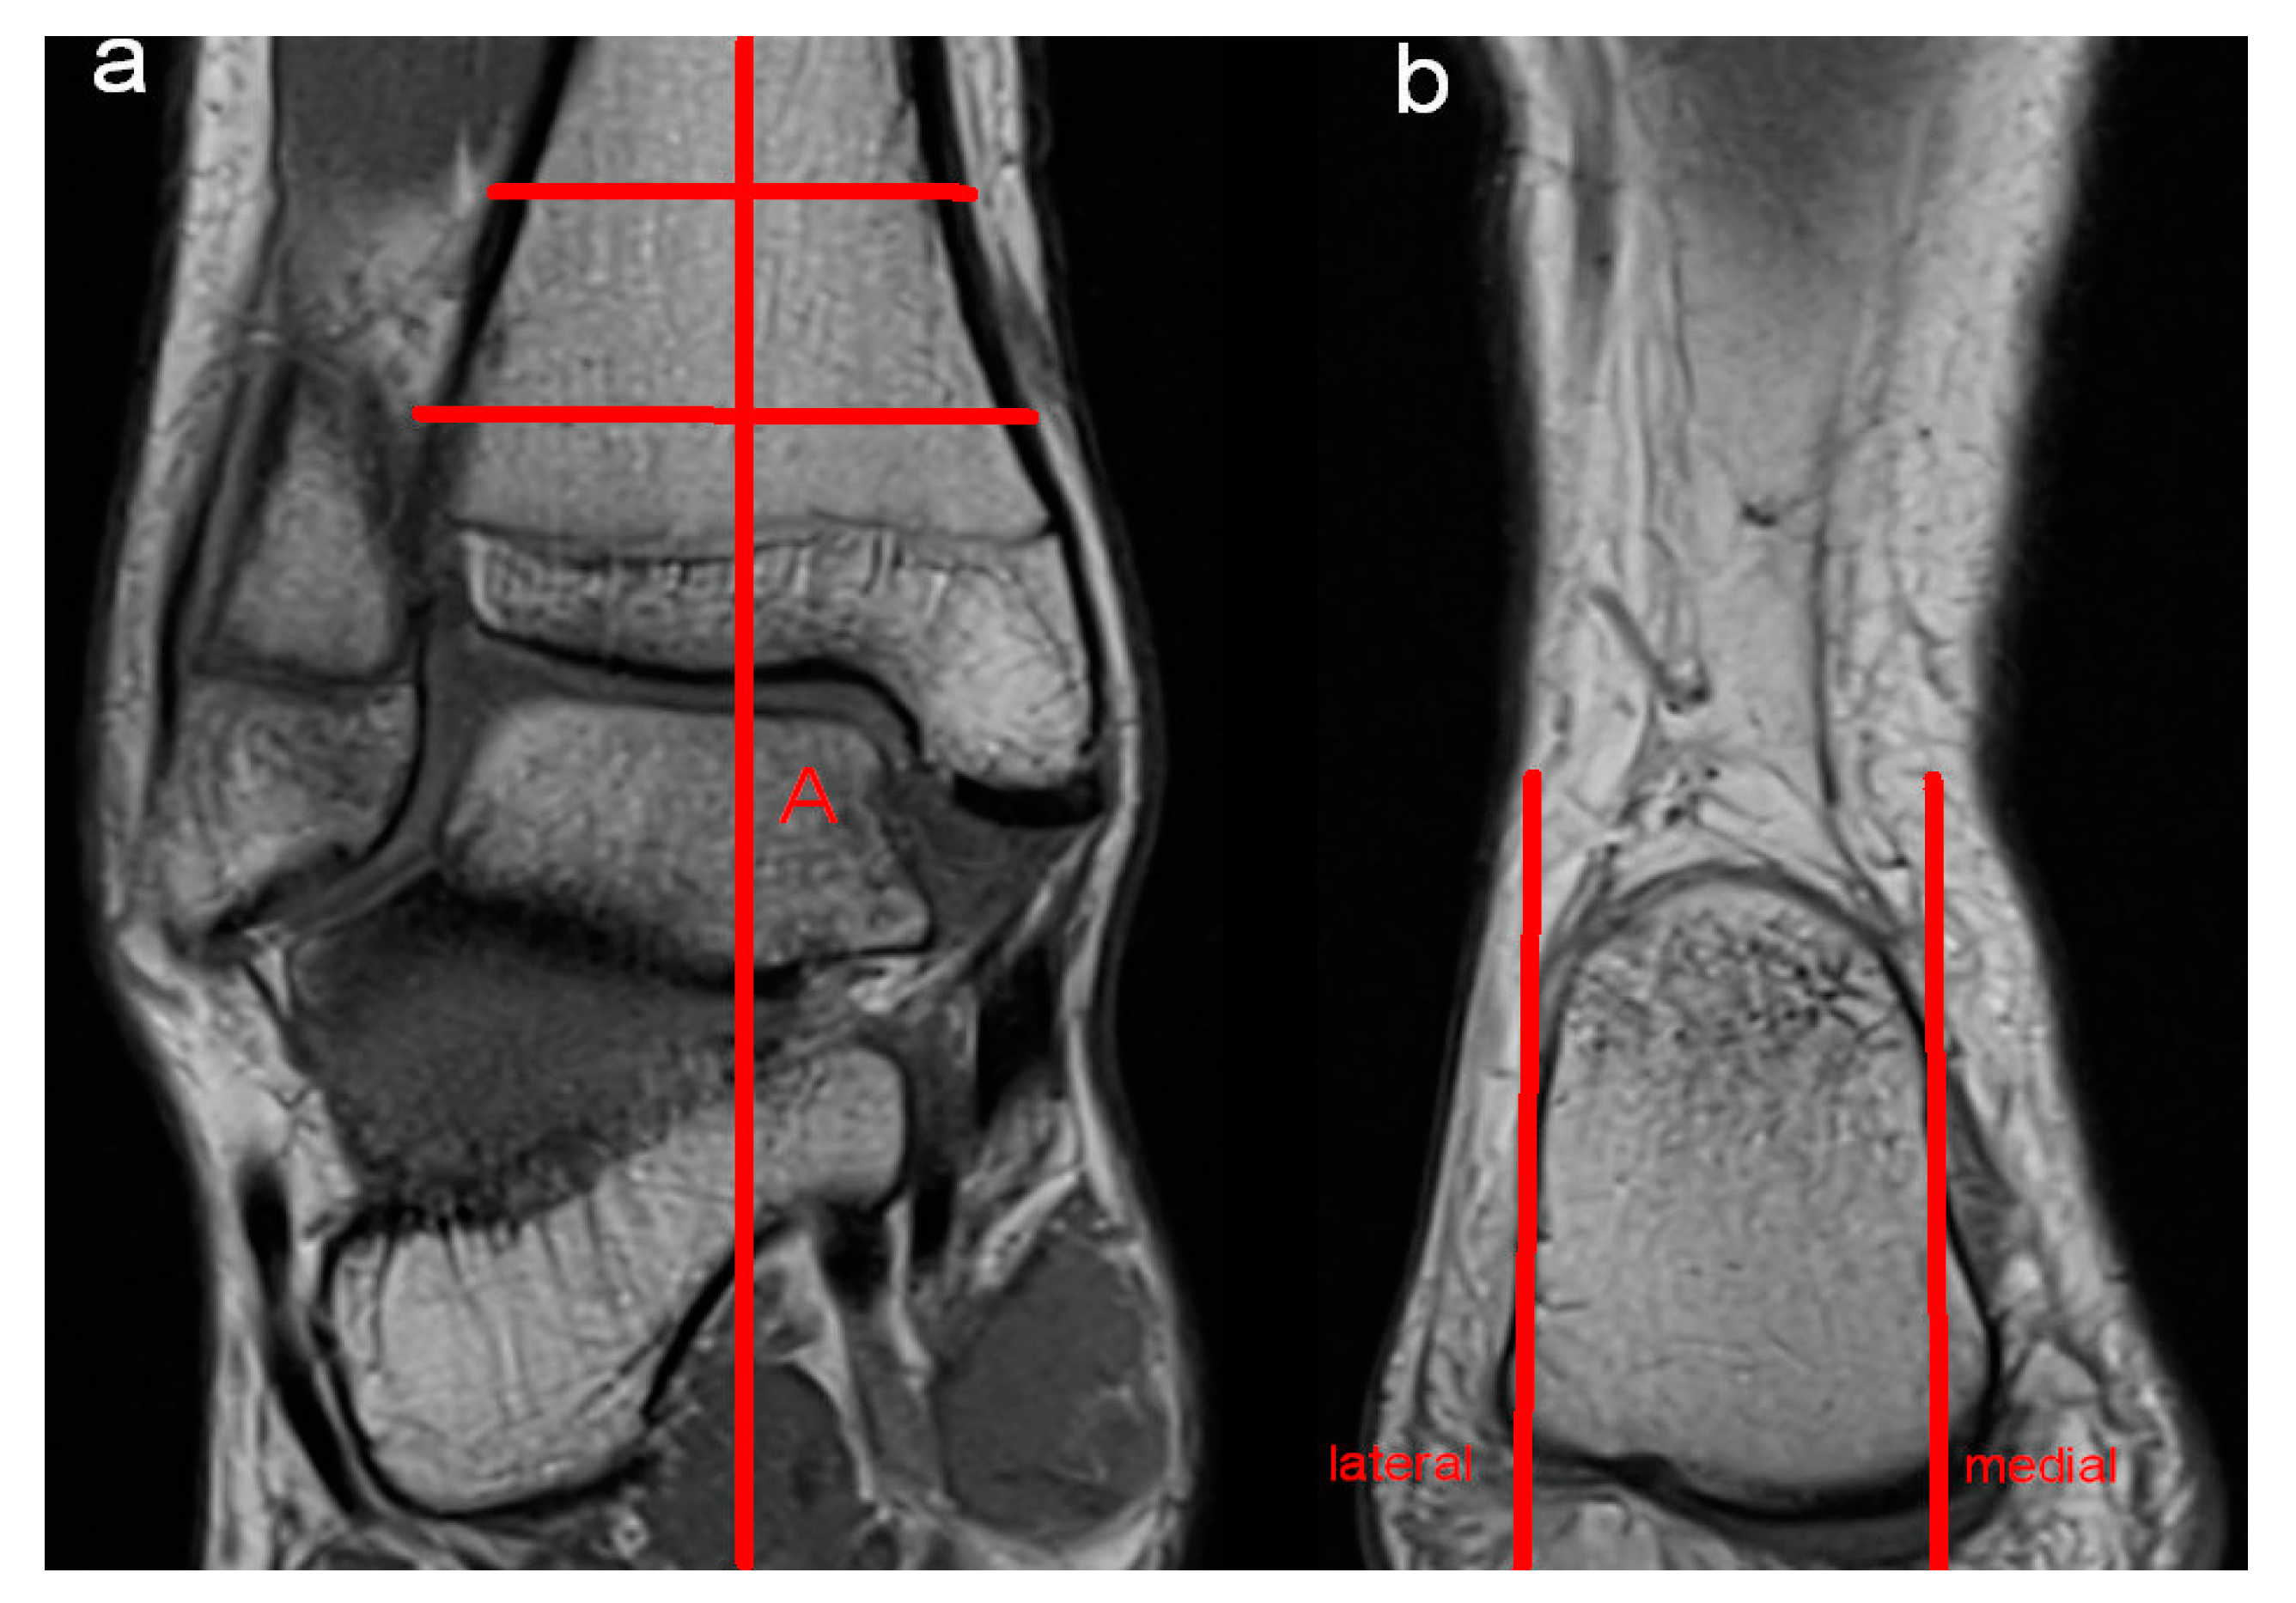

Figure 1. Hindfoot valgus was evaluated by measuring the angle between the tibial shaft axis (A) (a) and a line adapted to the medial and lateral surfaces of the calcaneus (b).

Moreover, potential anatomic risk factors for the development of perspective ankle complaints were assessed. MRI evaluation included abnormalities of the bone, the ventral and dorsal syndesmosis, the collateral ligaments, ligamentum bifurcatum, cartilage (modified Outerbridge classification; Grad I: cartilage with focal inhomogeneities but without substantial defect; Grade II: focal defect up to 50% of the cartilage height; Grade III: focal damage > 50% of the cartilage height without total height reduction; Grade IV: presence of an area with complete height reduction in cartilage), Osgood Schlatter disease, articular effusion, tarsal coalition, flexor and extensor mechanisms of the ankle (rupture or partial rupture of muscles or tendons, tendinopathy), bursa subachillae, plantar fascia and other intra-articular abnormalities, such as the presence of intra-articular loose bodies. Furthermore, impingement (anterolateral, anterior, medial and posterior) of the ankle was assessed. Impingement was diagnosed if the distance of the joint cavity was measured < 2 mm in the respective part of the joint. A reduction in the joint cavity could be caused by soft tissue or by the articulating surfaces themselves. To diagnose anterolateral impingement, the anterior joint cavity between the distal fibula and the distal tibia was evaluated by axial and coronal imaging. Sagittal and axial imaging was used to assess anterior impingement between the anterior part of the distal tibia and the talus. Coronal and axial imaging was evaluated to diagnose medial impingement between the malleolus medialis and the medial shoulder of the talus. Sagittal and axial imaging was used to assess posterior impingement between the dorsal part of the distal tibia and the processus posterior tali and/or the calcaneus. Moreover, hindfoot alignment was evaluated radiologically by coronal imaging. Referring to the findings of Buck et al., hindfoot valgus was assessed by the angle between the tibial shaft axis and a line adapted to the medial and lateral surfaces of the calcaneus. An angle > 11° was defined as hindfoot valgus malposition. Hindfoot varus was evaluated by the angle between the tibial shaft axis and a line drawn at a tangent from the tip of the sustentaculum tali to the plantar medial surface of the calcaneus. Values < 12° were defined as hindfoot varus malposition [12]. Figure 1, Figure 2 and Figure 3 illustrate the mentioned measurement methods.